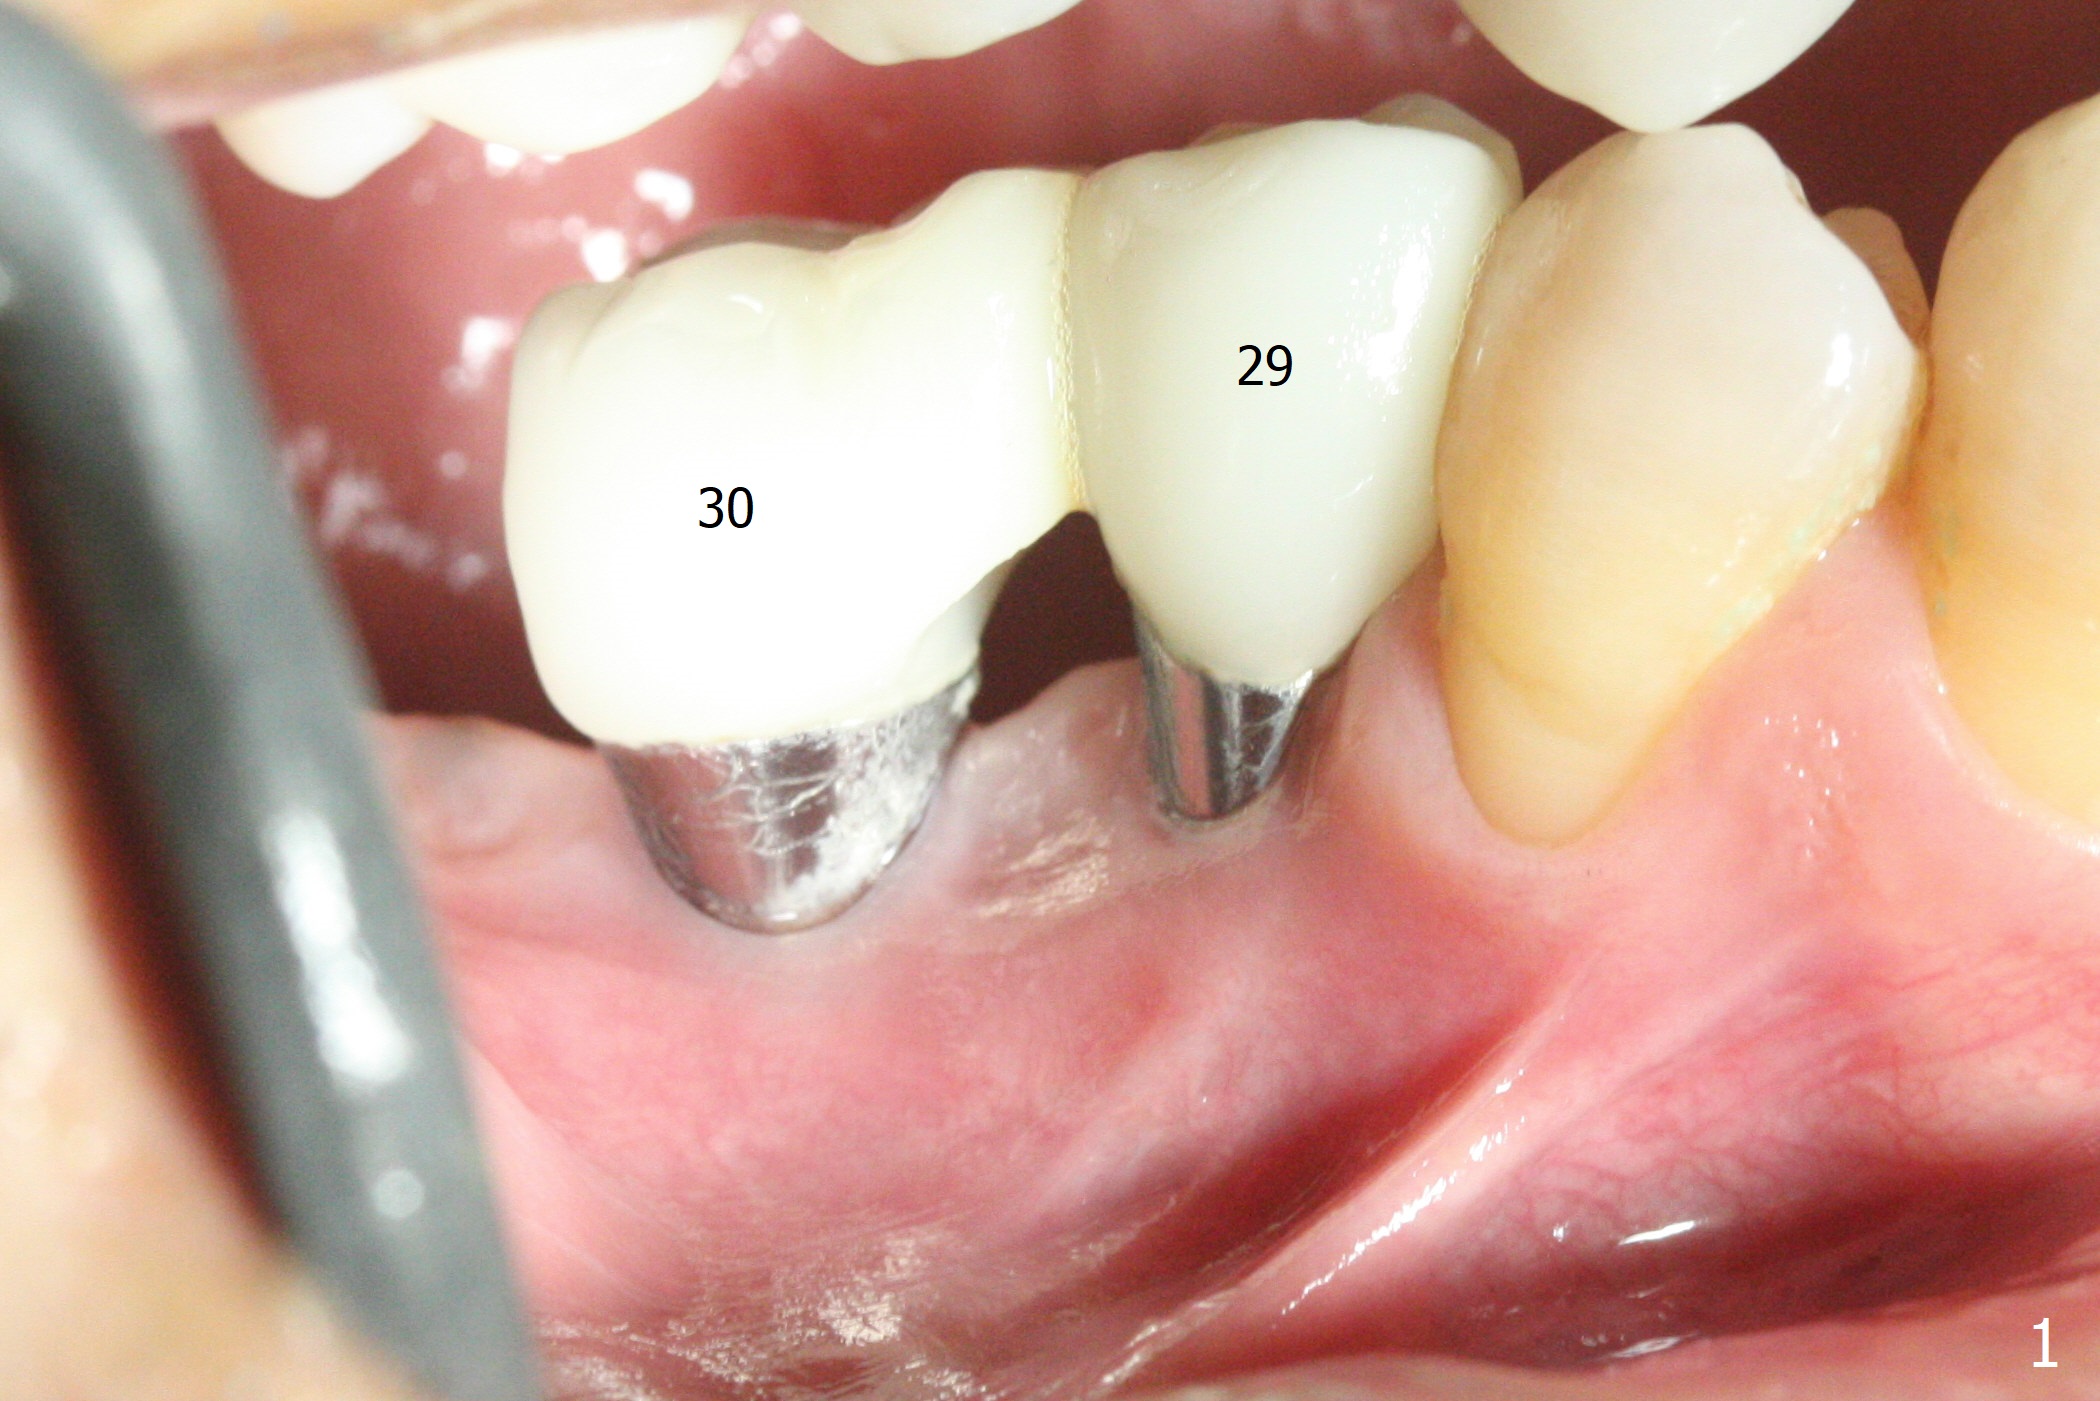

The buccal gingiva is recessive at #29 and 30 (Fig.1). Incision reveals buccal implant thread exposure with circum-ferential granulation tissue (Fig.2 *). Immediate post implant removal at #29, osteotomy is initiated lingual (Fig.3 (intraop CT, coronal section) ). A smaller and shorter implant (3x12 mm vs. 3.5x13 mm) is placed away from buccal (Fig.4 B, 5).

The implant at #30 was also buccally placed (Fig.6,7) and should be corrected in the same manner (Fig.7 green). Due to the bone being harder in the molar region, a smaller and shorter implant (4x11 mm vs. 5x13 mm) shifts slightly buccally while being placed (Fig.8,9). Since primary stability is lower (<20 Ncm vs. 35 Ncm associated with the implant #29), an abutment is not placed, which may be favorable to healing, but it is difficult to achieve primary closure. After bone graft (Fig.9 *) and 2 layers of PRF, Cytoplast is placed. Cytoplast appears to be exposed buccally (Fig.10 <) and occlusally (Fig.11 ^) asymptomatic 9 days postop. Exposure of Cytoplast is more distinct without sign of infection 15 days postop (Fig.12). The patient returns with chief complaint of "foul smell" 7 weeks postop (coronavirus lockdown). Although the Cytoplast exposes more (Fig.13 (* exposed; @ unexposed)), the underlying gingiva remains healthy (Fig.14). While the bone height decreases at #29, the bone density at #30 increases 4.5 months postop (Fig.15). The gingiva heals. The implant at #30 is uncovered 6 months postop. The lingual plate has to be removed for the uncover, while the coronal end of the buccal one is missing. No bone graft is added. When the 4.5x4 mm healing abutment is removed 6.5 months postop, the buccal plate looks concave at #30 (Fig.16' *). The buccal plate looks thin at #29 with a cotton roll placed buccally (Fig.16 R). The lingual plate at #29 is coronal to the buccal one (Fig.17). The buccal gingiva at #29 is quite long (Fig.18). The coronal buccal plate appears to be missing (Fig.19 >), which will be watched. A 4.5x7.5(4) mm cemented abutment is torqued (Fig.20).